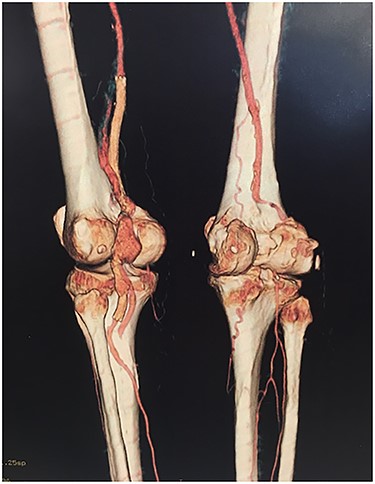

Approval for retrospective reports is not required by our institutional review board. This study is in accordance with the principles of the Declaration of Helsinki. A 77-year-old man with multiple comorbidities, including coronary vascular disease, hypertension, dyslipidemia, previous right carotid endarterectomy, and endovascular aortic repair (in 2011), was referred to our unit for evaluation of a retropopliteal pulsatile mass. He had undergone infra-popliteal stenting 18 months earlier, to treat peripheral arterial disease with severe left claudication. The procedure was performed at another vascular institute, and the stent type was unknown. Physical examination revealed the presence of a femoral and popliteal pulse and the absence of tibial pulses; at admission, the ankle–brachial index was 0.8. According to the patient, he had noticed the mass in the last 2 months prior to admission, but the absence of pain delayed his presentation to the hospital. An ultrasound scan was performed on admission and revealed a large popliteal pseudoaneurysm with normal flow present distally, and fracture of the stent was confirmed by computed tomography, which also detected a 4.2 cm dilatation of the left popliteal artery (Figs 1–3).

Angiotomography revealed fracture of a stent deployed in the popliteal artery and a pseudoaneurysm formation of size 4.2 cm at the part of stent fracture.

Angiotomography of the popliteal region highlighted the complete stent fracture and a large pseudoaneurysm formation.

Angiotomography showing a fractured stent and pseudoaneurysm at the site of the fracture.